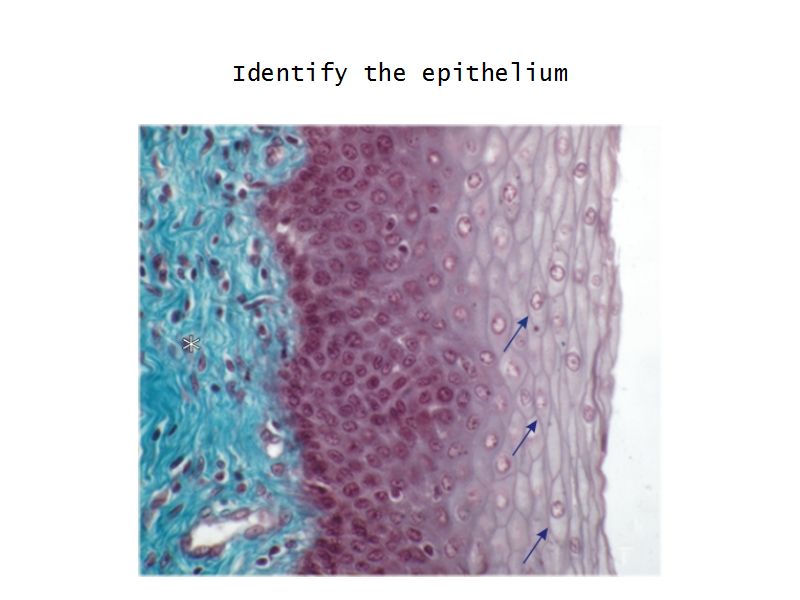

Mucosa

- Epithelium

- Thick stratified squamous nonkeratinized

- Lamina propria

- Fibroelastic connective tissue

- Rich in elastic fibres

- Contains lymphoid elements

- Deep portion highly vascular

- No glands